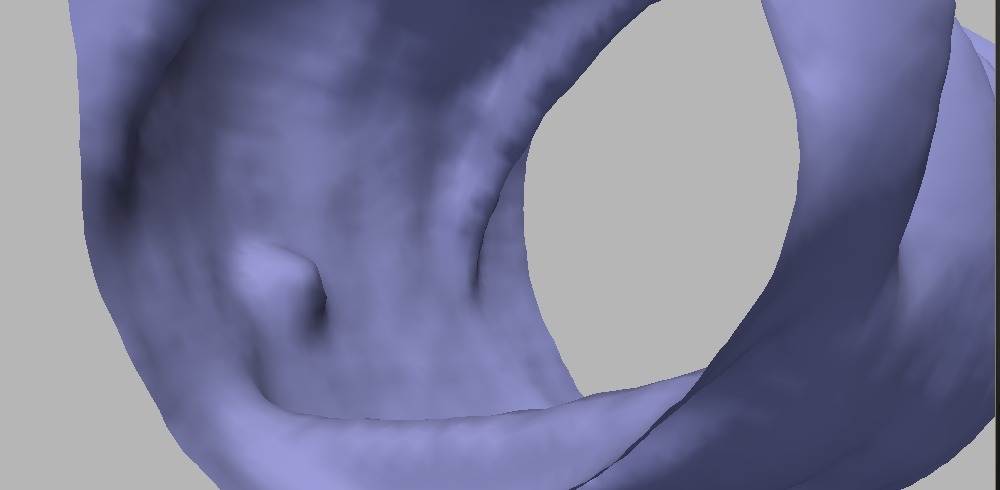

The air-fluid-tissue joint may create artifacts in the segmentation. This is a critical point, not only because of the quality of the segmentation, but mainly for the potential of yielding several false positives in the polyps detection step. It is not rare that segmentation algorithms result in “gutter-like” shapes along this interface. This improvement is crucial, since if small oscillations occur along the “gutter” (which is expectable due to the resolution of the CT image), artifacts with polyp-like shape are produced, and this, of course, degrades the performance of the whole CAD system. We paid particular attention to this issue while designing the segmentation algorithm: the computation allows to avoid these artifacts. Figure 4 illustrates the performance of our segmentation method compared to another version that presents some problems along this interface. The aim of the comparison is not to discuss which segmentation is better, but to show that our algorithm presents a smooth surface along the place where the gutter is expected to be.

II-B Smoothing and colon surface computation

In order to eliminate noise and to obtain a smoother colon surface after the segmentation stage, we proceed to smooth the initial segmentation . In this section we derive a PDE-driven smoothing technique that preserves the shape of the polyps, while obtaining a smooth enough surface to reliably compute local geometric features such as curvatures. Of course, the ultimate goal of the method is to simplify and to improve the polyp/non-polyp classification system. The effectiveness of the proposed approach will be assessed with experiments both qualitatively and quantitatively in Section V, where ROC curves obtained with the proposed PDE and other filtering alternatives will be compared.